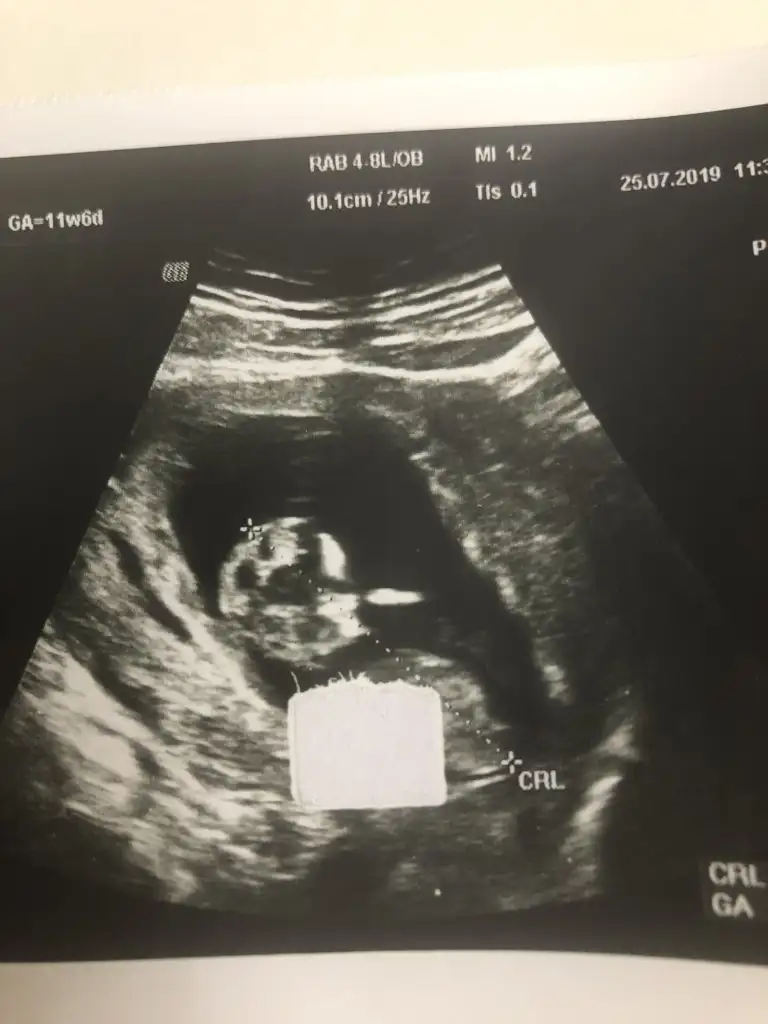

Erkek gibi11 haftalıktahmin alabilirmiyim

Cevabin icin cok tesekkur ederim canim.Tutma ihtimali yüksek erkek olma ihtimali de yüksek cnm

ErkekMerhaba arkadaşlar bu başka birinin bebeği . Rica etsem bu bebeğide tahmin edebilir misin?![]()

Teşekkür ederimErkek gibi